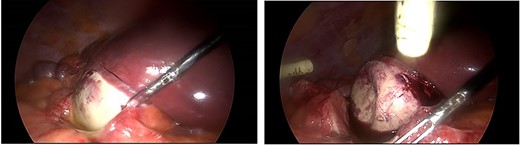

Laparoscopy revealed an acutely inflamed porcelain gallbladder (Fig. 2). Laparoscopic dissection of Calot’s triangle was difficult due to inflammation and the decision was made to convert to an open operation to complete the cholecystectomy safely. A fundus first approach was employed and the cystic duct was found to be obliterated by an impacting gallstone. To minimise the risk of common bile duct injury, the decision was made against further dissection of the cystic duct stump. The cholecystectomy was completed, and a drain was left in the subhepatic space.

Intraoperative images demonstrating an inflamed porcelain gallbladder.